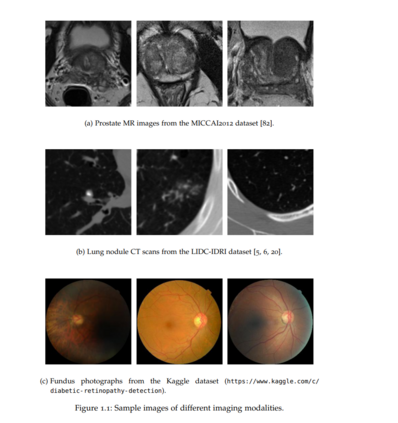

**本文共分为4个独立章节,分别研究面向医学图像分割与重建的不确定性量化方法、面向生存分析的鲁棒深度模型和新的灰盒对抗防御算法。**该论文结合了理论和实证结果,包含了医疗健康中的两个应用,即医学图像分析和生存分析。**在第3章和Hu et al.[54]中,提出了一种新的医学图像分割的监督不确定性量化方法。利用多级标注的可变性作为"基础真相"偶然不确定性的来源,并将其视为监督学习问题中的目标。**我们将这种基本事实的不确定性与概率U-Net[69]相结合,并在LIDC-IDRI肺结节CT数据集[5,6,20]和MICCAI2012前列腺MRI数据集[82]上进行测试。我们发现,我们能够改进预测的不确定性估计。我们还发现可以提高样本精度和样本多样性。**在第4章和Hu、Pezzotti和Welling[53]中,我们提出了一种新方法,可以准确评估医学图像重建模型的预测精度。**首先,通过将预测误差分解为随机误差和系统误差,证明当前方法估计的预测不确定性与预测误差不高度相关,并表明前者等价于随机误差的方差。目前的方法通过修改模型结构和训练损失来联合估计真实目标和数据的不确定性,从而不必要地损害了性能。分别估计它们而不进行修改可以提高性能。接下来,建议分两步估计目标标签和预测误差的大小。在一个大规模的MRI重建数据集[127]上展示了所提出方法,取得了比最先进的不确定性估计方法更好的结果。